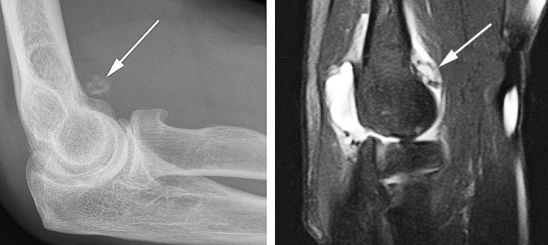

На МРТ локтевого сустава при любом переломе видна реакция костного мозга. Это помогает в диагностике, если перелом сразу не виден на рентгенограмме. В дальнейшем можно прицельно дообследовать подозрительную область. При консолидировавшихся переломах на МРТ остается видна линия перелома, а окружающий костный мозг нередко подвергается жировой дегенерации. МРТ в СПб стало необходимым компонентом обследования пациентов с травмой суставов и осуществимо в высоких полях или открытом МРТ. МРТ СПб дает возможность исследовать методом МРТ локтевой сустав в разных центрах, однако, наш опыт позволяет рекомендовать обследование именно у нас.

Рентгенограмма (слева) и МРТ локтевого сустава (справа). Суставная мышь (стрелка). Выпот и синовит на Т2-взвешенной МРТ.